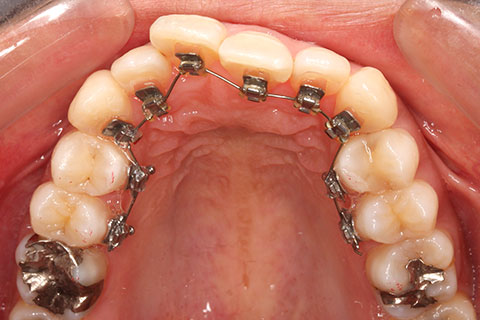

治療中(開始直後)

治療中(開始半年後)